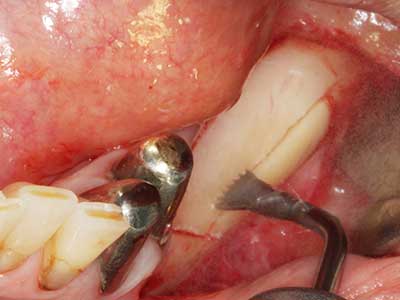

Fig. 18: Preparación de una tapa cortical con la sierra ósea piezoeléctrica (Piezomed, W&H).

Fig. 19: Zona operada después de neurolisis y eliminación del osteomo.

Fig. 20: La tapa ósea extraída se readapta y se fija mediante un tornillo para osteosíntesis (KLS Martin, Tuttlingen).